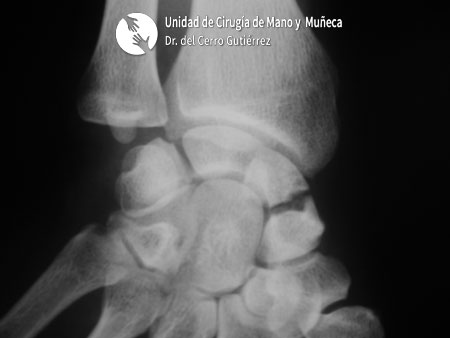

Fractura del Escafoides